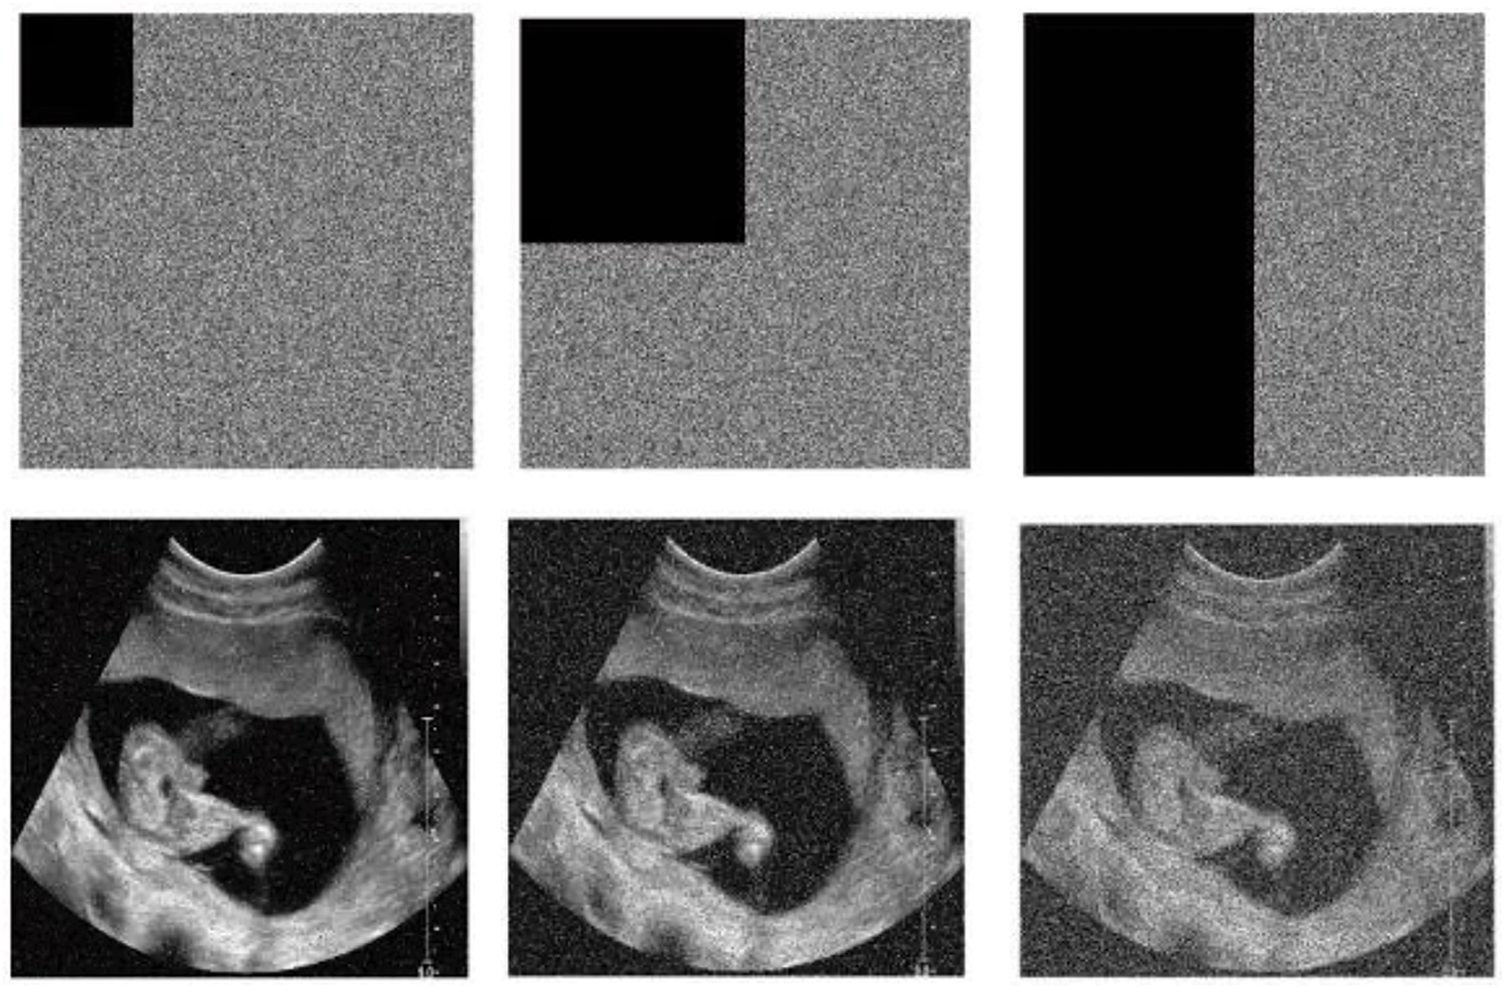

Images are generally subject to various attacks during transmission and sometimes storage. These attacks range from modification, occlusion, or shearing with the aim of causing the loss of image information. When an encrypted image is attacked by occlusion, the robust cryptosystem must be able to recover important information from the original image. To test the robustness of the proposed technique to shear attacks, the encrypted child sonography image was cropped by 1/16, 1/4, and 1/2, respectively. The corresponding visual result for the child sonography image is depicted in Fig. 6. In addition, the PSNR values of all the test recovered and encrypted images are listed in Table 6. From this table, it can be seen that the PSNR of the recovered image is higher than that of the encrypted image, regardless of the loss fraction data, which ensures the robustness of the cryptosystem to occlusion attacks.

Figure 6: Occlusion attack results for child sonography image